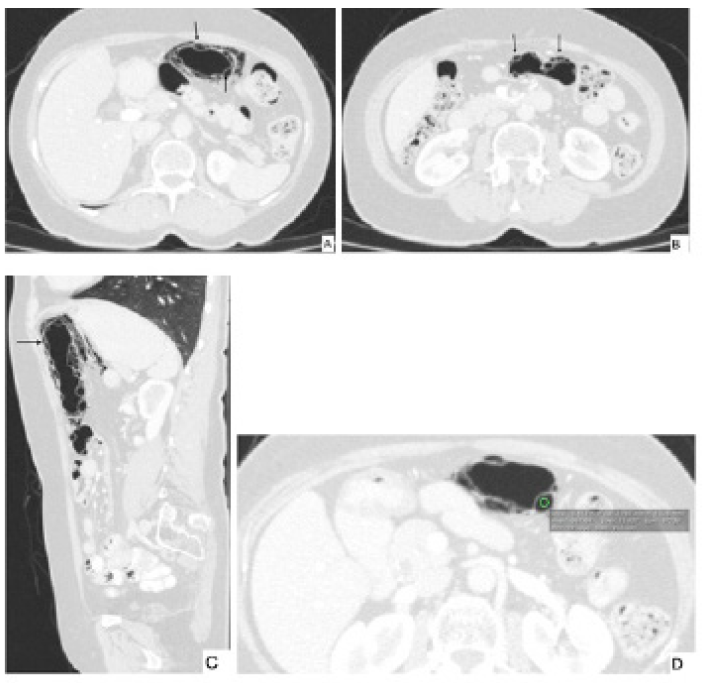

El patrón que más se ha asociado a enfermedad benigna es el patrón circular (quístico) 2,7,8, el cual es mas común en el colon y está descrito en neumatosis intestinal quística 2,9,14. Por el contrario, el patrón lineal fue descrito por Kernagis et al. cuando ocurre infarto transmural 2 (figura 3) y está relacionado en el tipo secundario 7. El patrón curvilíneo también se ha relacionado mas con formas severas 8.

Figura 3 a y 3b. Tomografía contrastada axial y coronal donde se observa aire transmural en el colon con patrón lineal. En la reconstrucción coronal hay líquido peri hepático y aire libre, hallazgos secundarios a isquemia colónica.

Hay otros hallazgos en la tomografía que ayudan a hacer diagnóstico de enfermedades severas, tales como engrosamiento de la pared del asa intestinal, liquido libre o estriación de la grasa y tejido blando adyacente, entre otros 1,2. Si los espacios quísticos de la pared se distribuyen en un segmento intestinal que sigue un territorio vascular es probable que el origen sea una enfermedad severa 2. Un signo de isquemia intestinal es la presencia de gas en el sistema porta 9. Este hallazgo también puede estar presente en el contexto de trauma abdominal, colecistitis crónica, colangitis, pancreatitis y postoperatorio de trasplante hepático 9. En la tomografía se definen hipo densidades lineales ramificadas en la periferia del parénquima hepático 1.